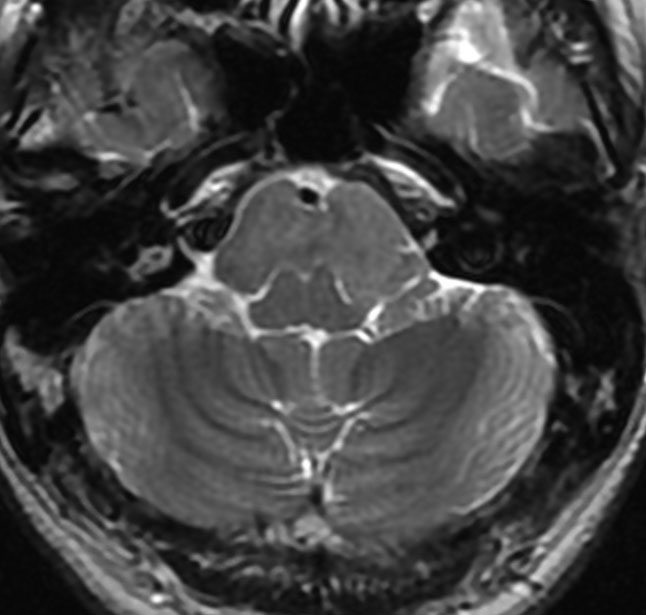

典型的な神経腸嚢胞 neurenteric cyst

左のT2強調画像で等信号,中のT2*で高信号,右はCISS画像です。

T1強調画像では,のう胞周囲の高信号の部分は半固体で,中心部の高信号はドロドロの粘液でした。基本的にガドリニウム増強はされません。まれに薄い膜状に一部が増強されることがあります。

境界明瞭は袋状の腫瘍です。椎骨動脈や脳底動脈を包み込むようにふくらんでいます。

左外側後頭下開頭という小さな開頭手術だけで全摘出しました。術後は幸い何の症状も出ていません。この例は脳幹部に食い込まないもので,運良く全摘できたのですが,そうはいかないものもあります。